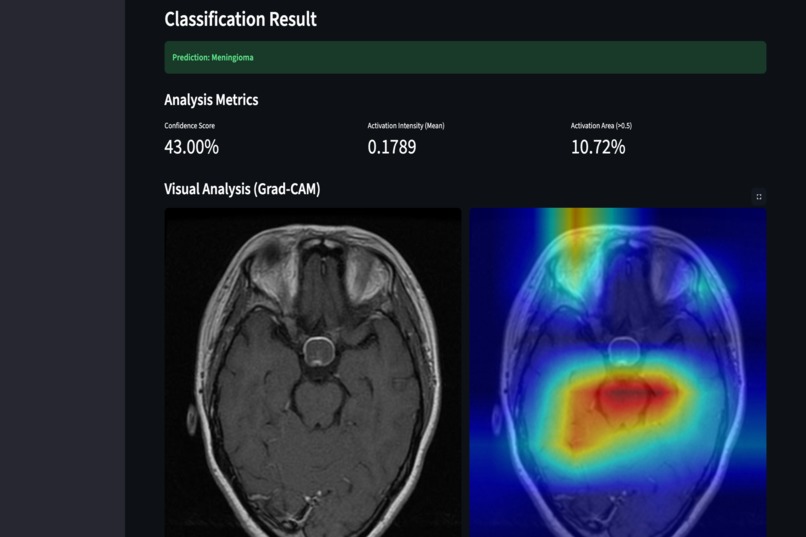

Results Webpage

To improve trust and transparency, the system also generates Grad-CAM visualizations that highlight which regions of the brain influenced each prediction.

- Integrated Grad-CAM for visual explanations and added quantitative explainability metrics

- Integrated explainability tools that provide clinically meaningful insights